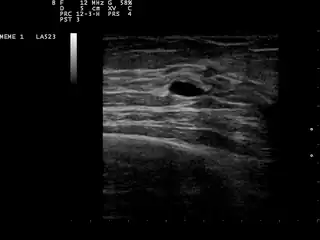

Quiste mamario

![]() Pequeño quiste mamario. Ecografía. | ||

La naturaleza quística de un bulto mamario se puede confirmar mediante ecografía, aspiración [8] (extracción del contenido con aguja) o mamografía. La ecografía también puede mostrar si el quiste contiene nódulos sólidos, señal de que la lesión puede ser precancerosa o cancerosa. El examen realizado por un citopatólogo del líquido aspirado del quiste también puede ayudar con este diagnóstico. En particular, debe enviarse a un laboratorio para que se analice si está manchado de sangre.

A las pacientes con sospecha de quistes mamarios normalmente se les realizará una mamografía de diagnóstico, aunque no se sospecha que tengan cáncer. Este tipo de mamografía brinda al médico la posibilidad de realizar una ecografía mamaria al mismo tiempo y es por eso que muchas veces se prefieren a las mamografías de detección. La ecografía mamaria se considera la mejor opción a la hora de diagnosticar quistes mamarios porque tiene una precisión del 95 al 100%, proporciona una imagen clara de la apariencia del quiste (simple o complejo) y también puede distinguir entre bultos sólidos y quistes llenos de líquido, que la mamografía no puede hacer. [9] Las ecografías mamarias se realizan con la ayuda de un instrumento médico de mano que se coloca sobre la piel, después de que se le haya aplicado un tipo de líquido especial. Los instrumentos captan el eco resultante de las ondas sonoras que envía al pecho. Estos ecos se transmiten a una computadora que los traduce en una imagen.